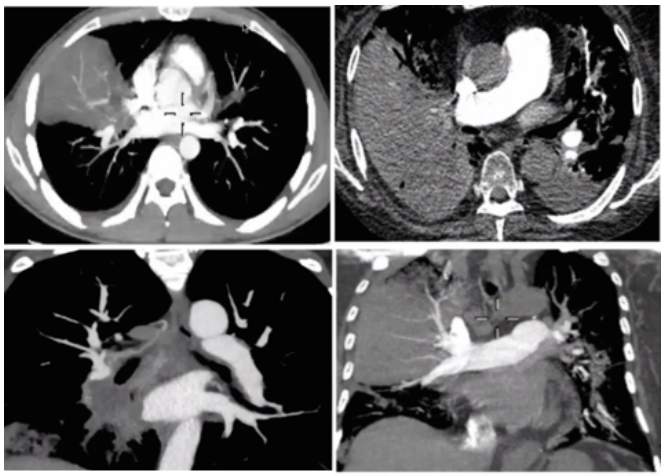

图片